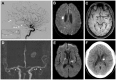

Primary angiitis of the central nervous system (PACNS) represents a rare inflammatory disease affecting the brain and spinal cord. Stroke, encephalopathy, headache and seizures are major clinical manifestations. The diagnosis of PACNS is based on the combination of clinical presentation, imaging findings (magnetic resonance imaging and angiography), brain biopsy, and laboratory and cerebral spinal fluid (CSF) values. PACNS can either be confirmed by magnetic resonance angiography (MRA)/conventional angiography or tissue biopsy showing the presence of typical histopathological patterns. Identification of PACNS mimics is often challenging in clinical practice, but crucial to avoid far-reaching treatment decisions. In view of the severity of the disease, with considerable morbidity and mortality, early recognition and treatment initiation is necessary. Due to the rareness and heterogeneity of the disease, there is a lack of randomized data on treatment strategies. Retrospective studies suggest the combined administration of cyclophosphamide and glucocorticoids as induction therapy. Immunosuppressants such as azathioprine, methotrexate or mycophenolate mofetil are often applied for maintenance therapy. In addition, the beneficial effects of two biological agents (anti-CD20 monoclonal antibody rituximab and tumour necrosis factor-α blocker) have been reported. Nevertheless, diagnosis and treatment is still a clinical challenge, and further insights into the immunopathogenesis of PACNS are required to improve the diagnosis and management of patients. The present review provides a comprehensive overview of diagnostics, differential diagnoses, and therapeutic approaches of adult PACNS.